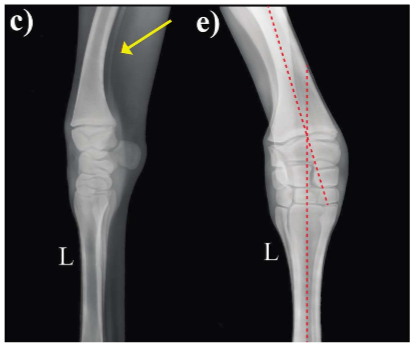

• angular limb deformities = Deviation from the long axis of the limb in the frontal plane, observed when foal viewed from in front or behind

• label the image

A) valgus

B) varus

• A persistent ulna causes an anchor on the lateral aspect of the limb preventing growth.

• This is common in Shetlands and miniature horses

• what is the yellow arrow pointing to?

a persistent ulna